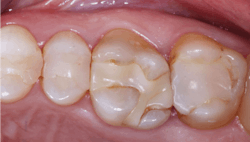

It has been estimated that about 90% of indirect restorations in the US are single crowns, and the majority of these single crowns are for posterior teeth. The phenomenal success of the original formulation of zirconia (3Y or Class 5 tetragonal zirconia) is now well proven. With the limitation of often less-than-desirable esthetic qualities, this material has become the most-used material for posterior crowns (figure 1).

- Zirconia with stains placed on the presintered ceramic and fired into the restorations: Currently only offered by select labs; this material is looking promising (figure 2)